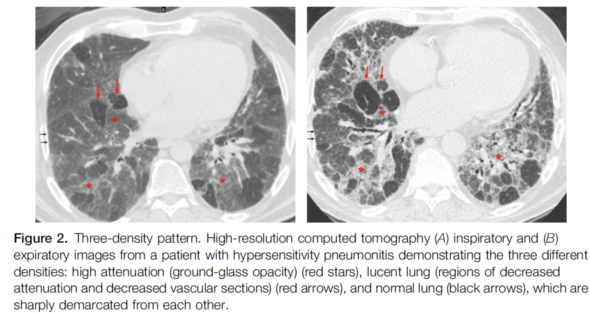

纤维化型HP与非纤维化型HP有一定的不同:呈纤维化型时,典型HP表现为不规则线状影、粗网格影伴肺扭曲、牵拉性支扩、蜂窝肺(不显著),不仅如此,还有小气道受累的疾病征象,比如小叶中央性结节/磨玻璃影、马赛克影、三种密度征、气体陷闭。

三种密度征(Three density pattern)里的三个区域分别是:高密度区提示磨玻璃影子,低密度区提示小气道疾病所累及的肺脏出现了气体陷闭的表现,还有一些正常的肺脏。

当出现三种密度征的时候,结合临床,能够高度提示这个患者是 HP。

这位慢性纤维化型过敏性肺炎患者就可以看到三种密度征、磨玻璃影、网格影、牵拉性支气管扩张,没有蜂窝。